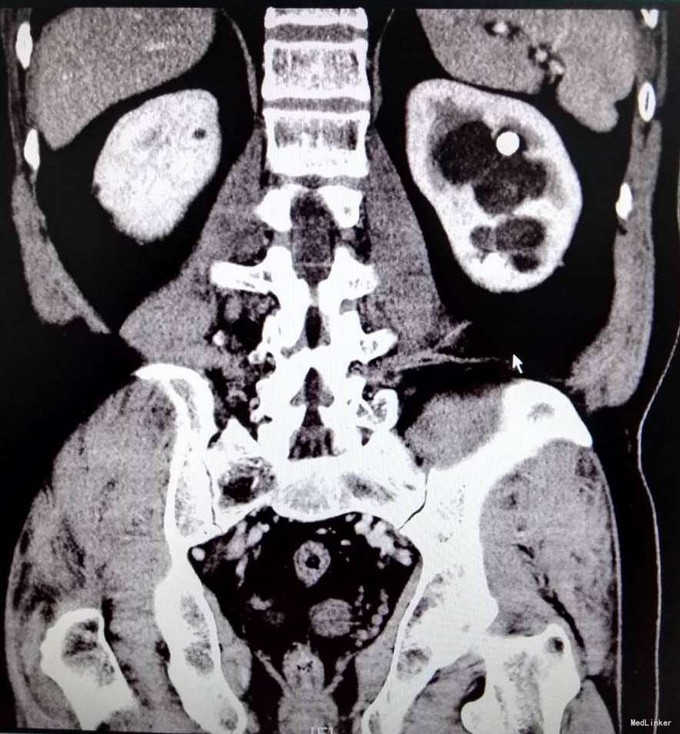

3、查体:未见明显阳性体征 4、辅助检查:外院平片:双肾多发结石;我院CTU:双肾多发结石,左侧肾盂输尿管连接处结石,并双肾积水,左肾明显,双侧肾盂、输尿管炎症。

5、诊断:肾结石(双肾多发结石) 6、治疗:入院后完善相关检查,双肾CTU:双肾多发结石,左侧肾盂输尿管连接处结石,并双肾积水,左肾明显,双侧肾盂、输尿管炎症。排除手术禁忌症后行左侧PCNL术,术后恢复良好,拔出肾造瘘管后,先出院休息,2周后返院进一步治疗